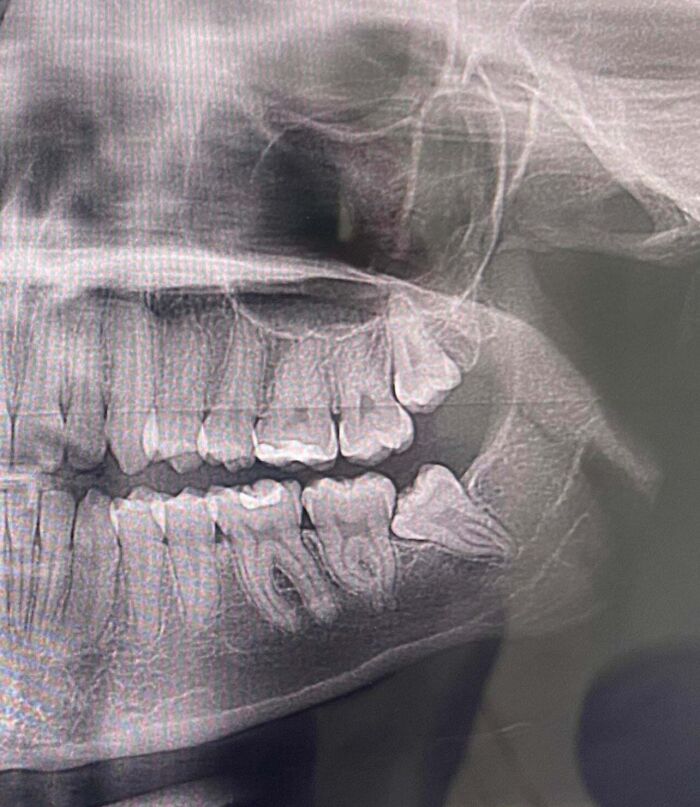

#1 Dentist Office Charged My Sister $500 For A CT Scan They Never Performed

Went in today to see the apparent CT scan taken last week compared to the current X-rays. The “current” CT scan is missing her implant that was put in 5 years ago…

Image source: parklover13